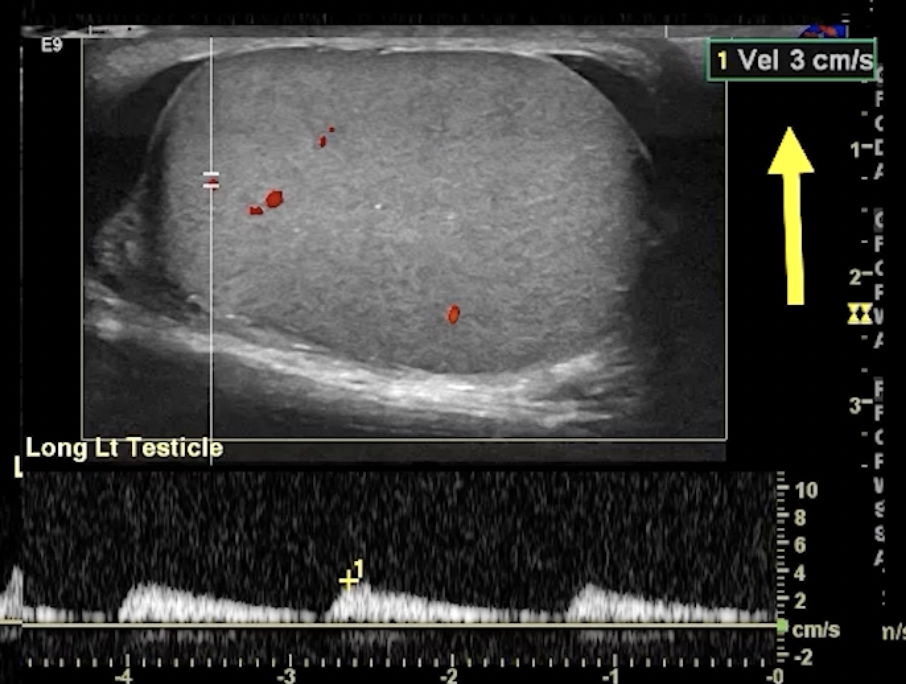

• Partial Torsion

• May have some blood flow

• Decreased or reversal of flow in diastole (no line in between peaks) - indicates high resistance state (top images)

• Blunted arterial peak (not as sharp as a point in systole) ( bottom images)